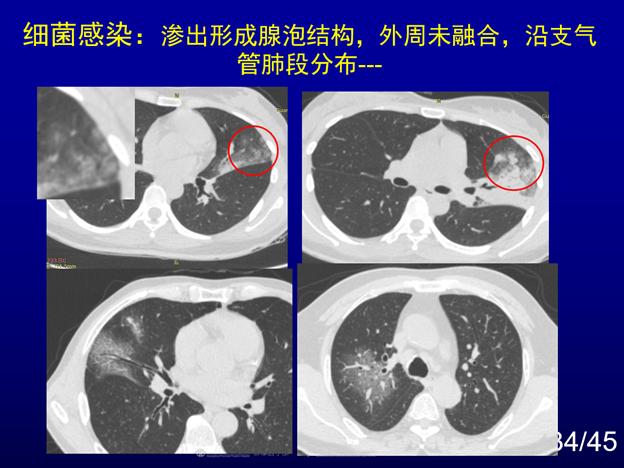

北京新冠肺炎动态更新及应对策略

摘要:北京新冠肺炎动态显示病例数量有所上升,但政府已采取积极应对策略。包括加强社区防控,提高检测能力,加强医疗救治和隔离措施等。公众也需保持警惕,遵守防疫措施,如佩戴口罩,勤洗手,保持社交距离等。北京正全力应对疫情,...